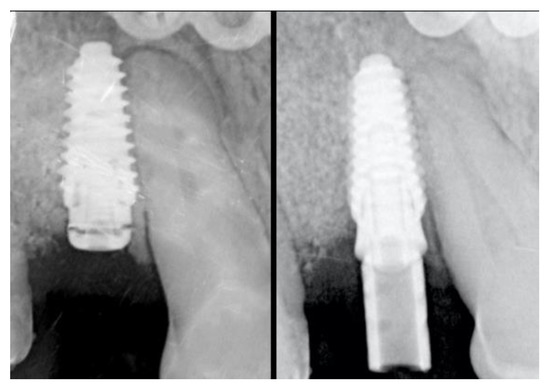

2.5. Re-Entry Surgery and Prosthetic Phases

2.8. Radiographic Assessment